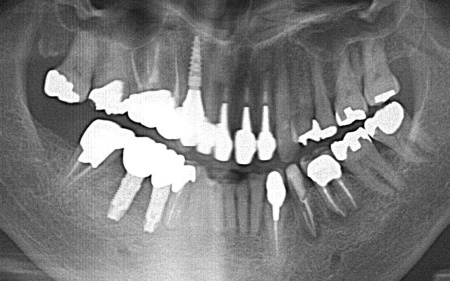

歯やあごの骨の状態を詳しく調べるためレントゲン検査を行った結果、右下の奥歯2本(第2小臼歯、第1大臼歯)は、歯根が縦方向に割れている可能性が高いと考えられました。

しかし、レントゲン画像だけでは歯根の状態を正確に判断することはできません。

次にCT検査を行い、骨の量や神経の位置を確認したうえでインプラント治療の計画を立てています。